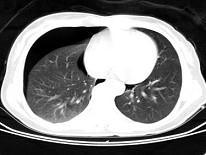

问题 男,35岁,胸部外伤,CT图像如图,最可能的诊断为 ( )

选项 A、右侧液气胸 B、右侧脓胸 C、畸胎瘤 D、右侧气胸 E、支气管囊肿并感染

答案 D